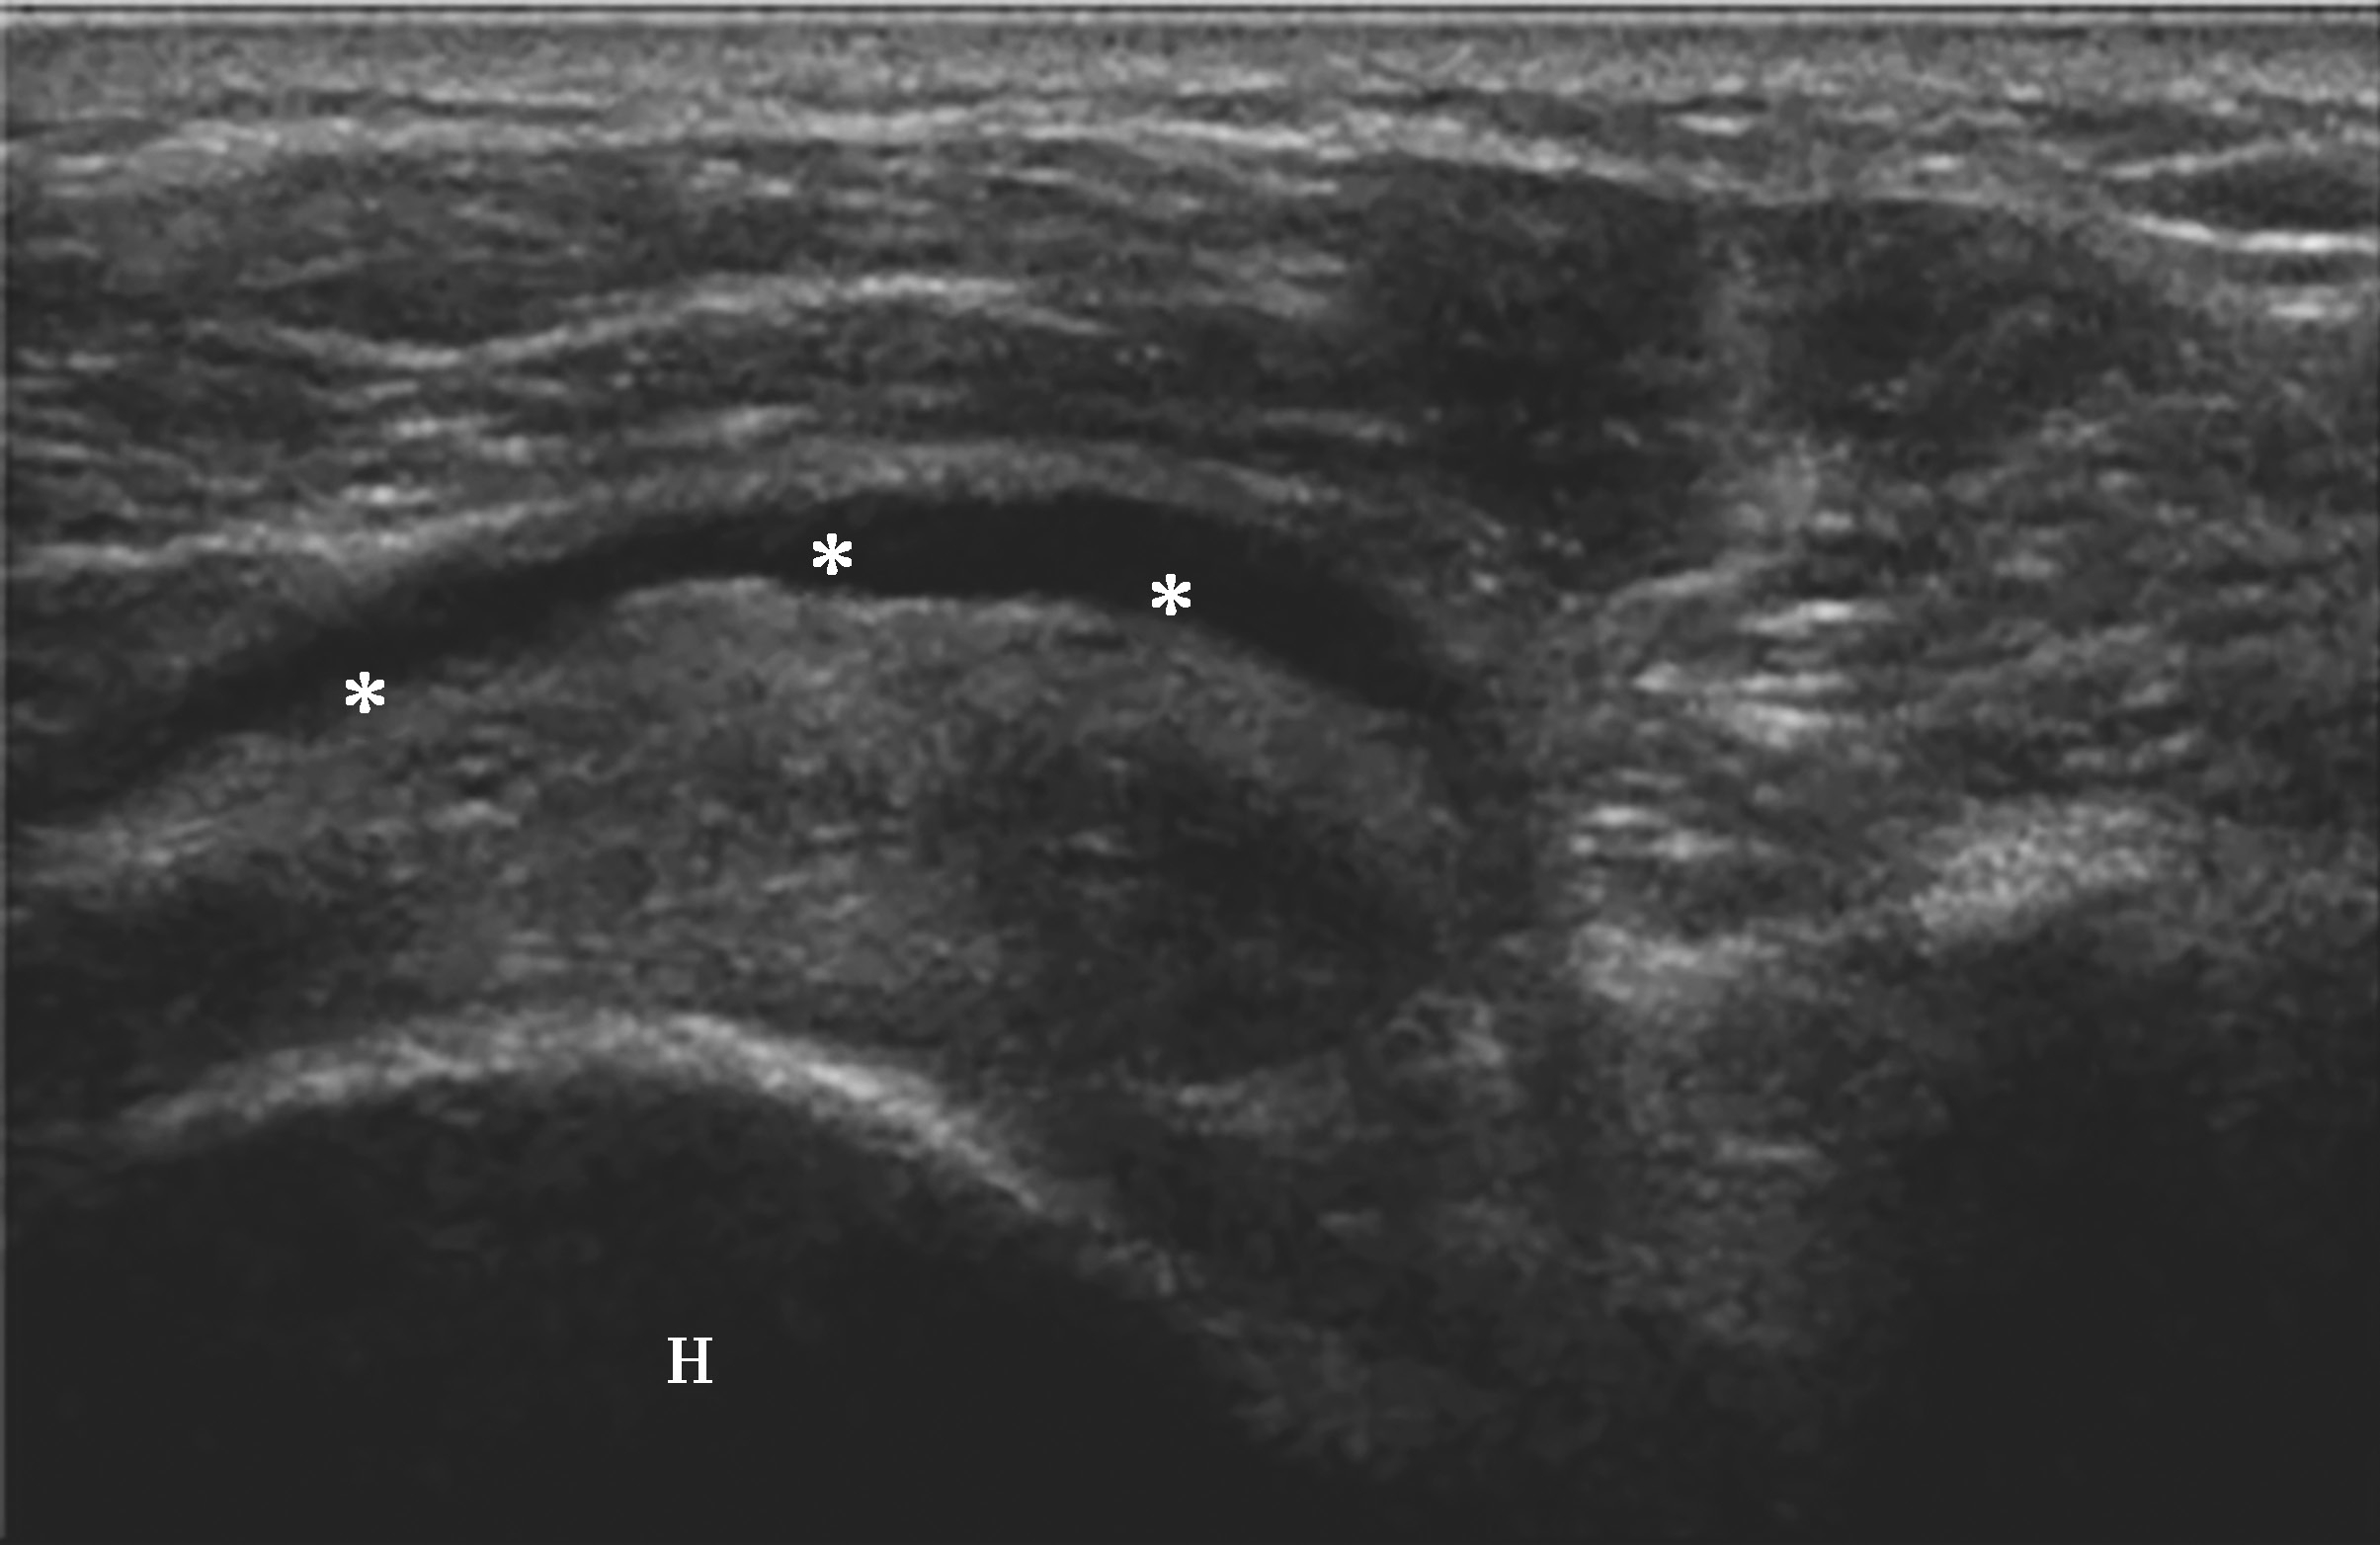

横放在肩关节前方,选择肩峰滑囊较厚或囊液较多处为靶目标(图2-1-2)。

▲ 图2-1-2 肩峰下-三角肌下滑囊炎超声图

星号:肩峰下滑囊增厚伴滑膜增生